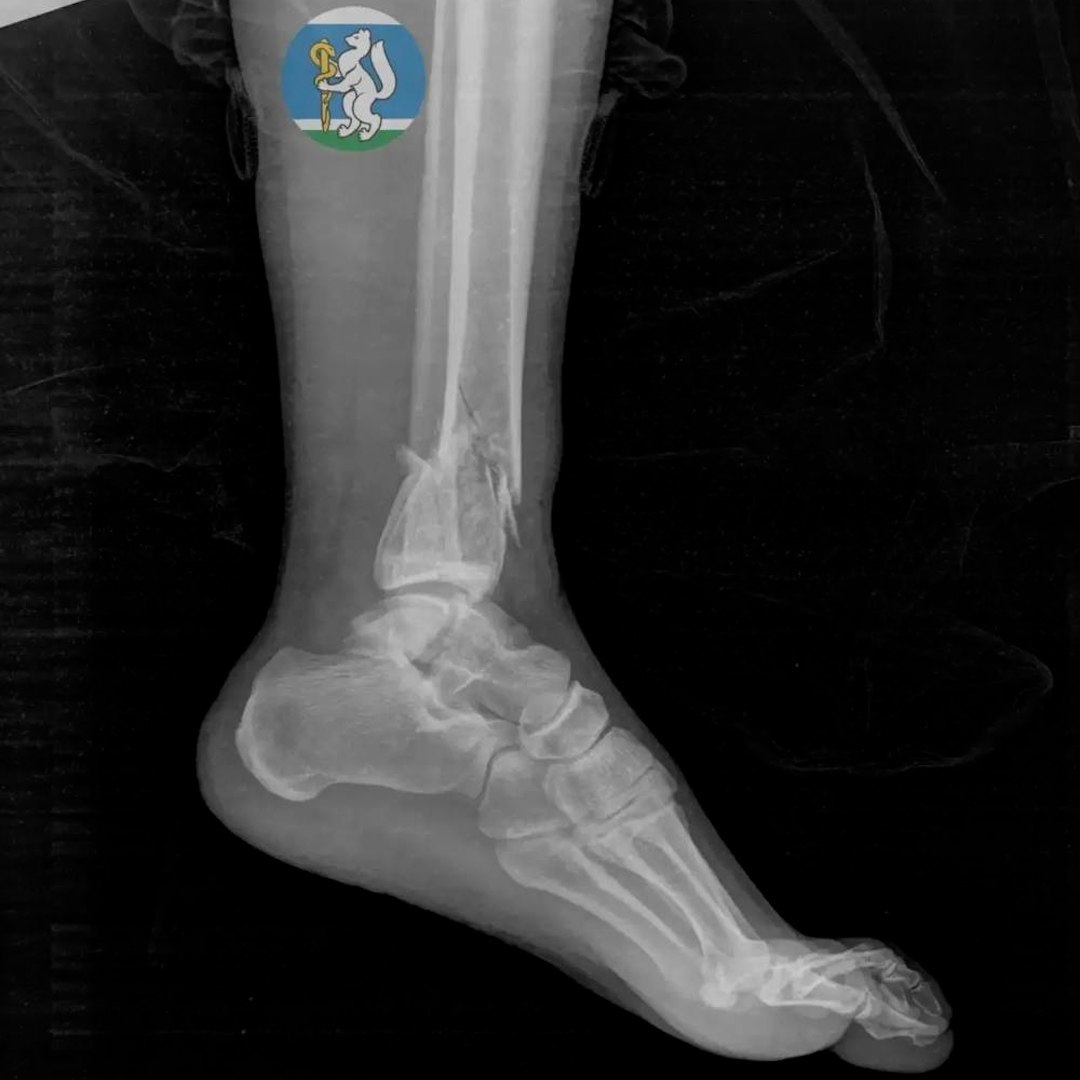

36-летняя женщина соскользнула c подоконника, когда мыла окна. Скорая забрала её с черепно-мозговой травмой, повреждением позвоночника, переломами таза и ноги.

Врачи реанимировали пациентку и провели ей несколько операций — работа шла несколько часов. Ещё месяц женщина приходила в себя в больнице. Сейчас она дома, проходит реабилитацию.